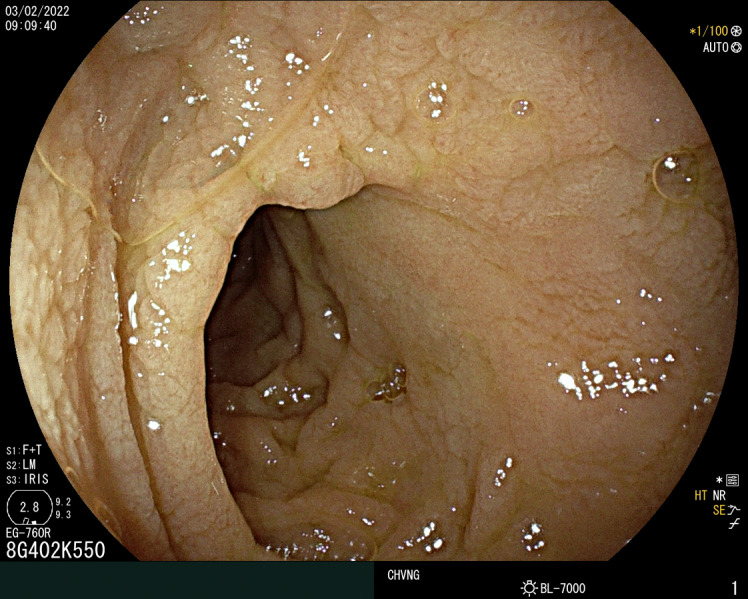

Common variable immunodeficiency enteropathy is a sprue-like disease, which may manifest as a severe malabsorption syndrome with nutritional deficits and cachexia. The authors report a case of a 33-year-old Afghan man, who presented to the emergency department due to chronic watery diarrhea and severe malnourishment. He had been previously misdiagnosed with celiac disease in his early adulthood; however, this was based on inconclusive findings. After a thorough diagnostic workup, the final diagnosis of common variable immunodeficiency enteropathy with symptomatic norovirus infection of the gut was obtained during his prolonged hospitalization. A slow but progressive improvement was observed with immunoglobulin replacement therapy, corticotherapy, and ribavirin treatment. This is a noteworthy case of a rare malabsorption disorder, and it reviews important aspects concerning the differential diagnosis of small bowel villous atrophy of unknown etiology, as well as gastrointestinal manifestations of common variable immunodeficiency disorder.